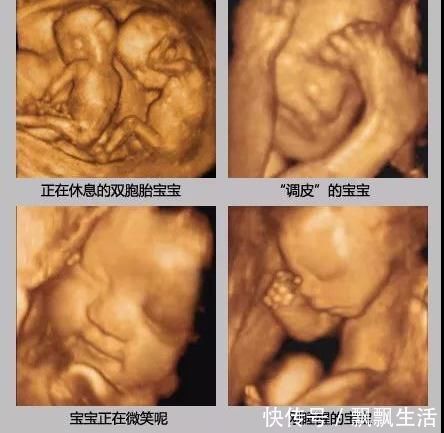

四维彩超一次不能顺利通过也不用太担心,大多是正常,可能胎儿睡着了、遮挡住了,可以吃点甜食、起来活动下再做一次,也可以另约时间再做。